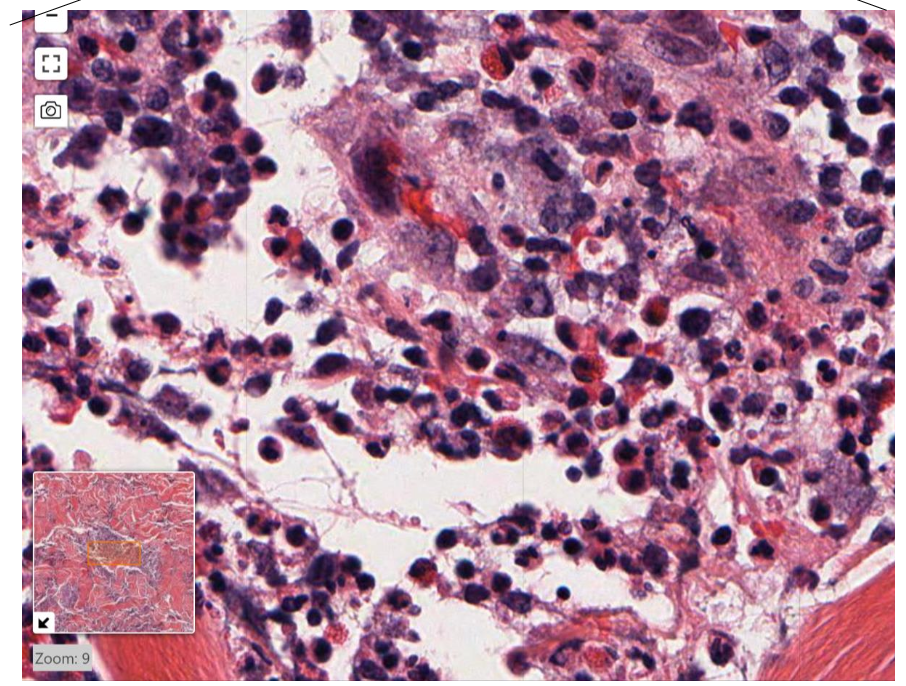

name the biological process shown in this image

acute inflammation

neutrophils !!